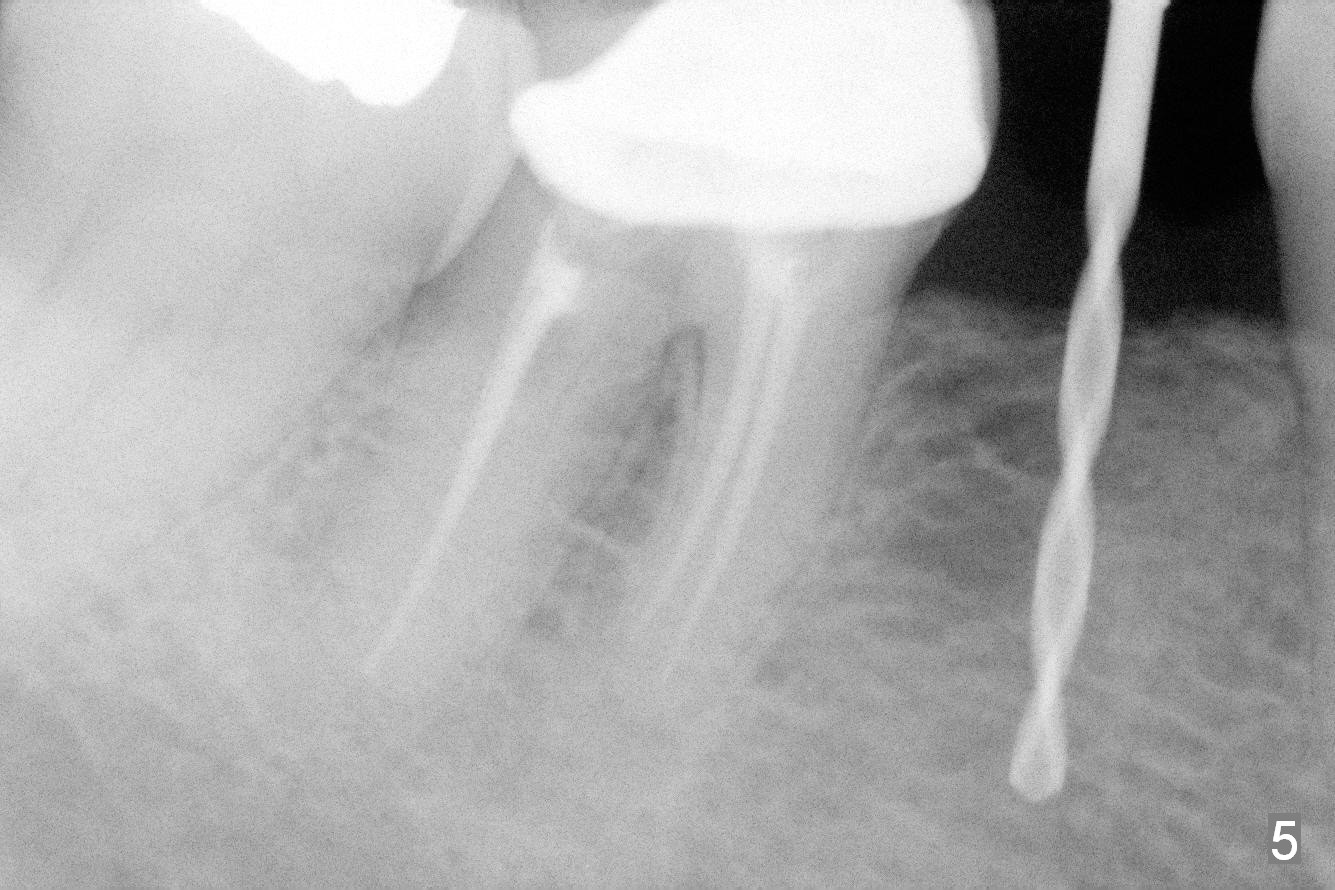

Preop photo shows the distal inclination of the tooth #28 (Fig.1).  The distal surface of the latter is reduced before incision for implant placement at #29 (Fig.2).  The buccolingual width is approximately 4 mm, as compared to 3 mm implant positioner (Fig.3).  After 1.2x10 mm osteotomy (Fig.5), the mesiodistal cortical bone is removed with a small high-speed fissural bur (Fig.4).  When a 2.5x12(2) mm 1-piece implant is placed (Fig.6), there is no buccal (Fig.7) or lingual plate perforation.  There is no postop paresthesia.  There is mild bone loss distal 4 months postop (Fig.8 *).  Take photos before and after permanent crown cementation to show increase in ridge width after bone graft and improvement in gingival health after provisional modification.  Take PA and/or BW post cementation to show that the distal bone resorption (Fig.8 *) is partially due to angulation.  No continuous bone loss 15 months post cementation (Fig.9).  There is mild bone resorption mesially 2 years 3 months post cementation (Fig.10).  The soft and hard tissues remain healthy 4 years 3 months post cementation (Fig.11,12).